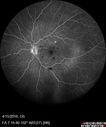

33 year old He noticed a new flash in the left eye. The flash started about 2 hours prior to the photos and he still notices it. The flash is in the center of the vision. The vision is not blurred. It's hard to tell because of the dilation. VA 20/12 OD and 5/200 OS. The vision remarkably improved to 20/16 within 1 month in the left eye. Blood tests showed a protein C deficiency.

Central retinal artery and vein occlusion - Protein C Deficiency 33 year old male493 views33 year old male with vision loss for 3 hours. VA 20/12 right eye, 5/200 left eye. He has a protein C deficiency. The left eye recovered vision in about 1 month to 20/16. FA shows very slow recirculation time.     (0 votes)